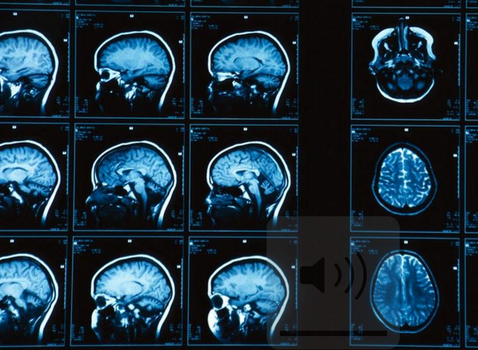

Scientists at Tel-Aviv University scanned the brains of 1400 people of mixed gender and found that although some features appear more in men than in women and vice versa, most people actually have a ‘mosaic’ like brain makeup with a lot of different traits.

(Featured Image: National Geographic)